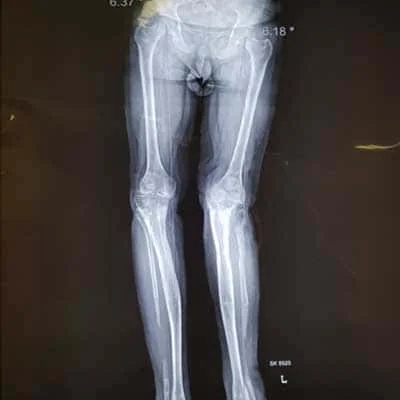

Complex Orthopaedic Surgery

• Removing the damaged articular cartilage (a plate that assists with smooth leg movement)

• Smoothening of the damage to the femur and tibia: These damages might be caused by degenerative diseases like arthritis.